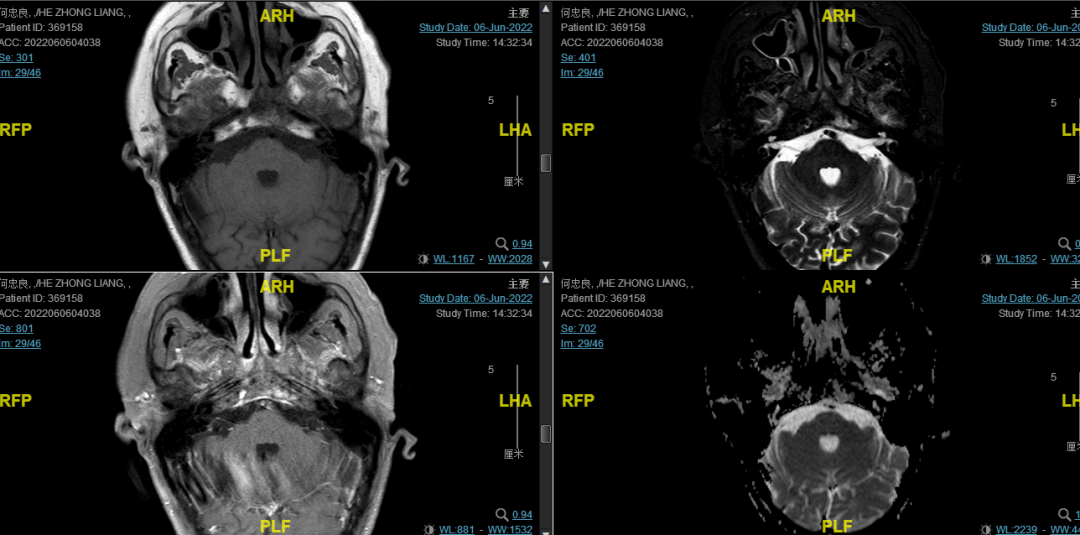

后患者至江苏省肿瘤医院放疗科就诊,2022-06-06完善头颅MR检查:

修正诊断:鼻咽癌T3N1M0,Ⅲ期。